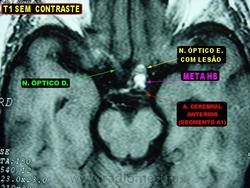

ГМ. Кавернома 2. Кавернома зрительного тракта. +

Кавернома зрительного тракта